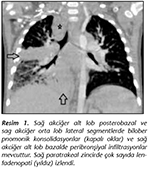

Yapılan tetkiklerinde� t�berk�lin deri testi (TDT) ve interferon gama salınım testi� (IGST) negatif bulundu. Ekokardiyografisinde sekundum tipte 9 mm ASD saptandı. Biyokimyasal testleri, ter testi, imm�nglobulin değerleri normal bulundu. Toraks BT'sinde mediastinal konglomere patolojik lenfadenopati, sol akciğer alt lobun tama yakınında hava bronkogramları ve yaygın konsolide alanlar saptanması nedeniyle a�lık mide suyu (AMS) alınarak epit�berk�loz tanısı ile izoniazid, rifampisin, pirazinamid tedavileri başlandı (Resim 1). Kontrollerine il dışında devam eden hastanın tedavinin altıncı ayında boynunda g�zlenen korteks kalınlığı artmış multipl servikal lenfadenopatileri nedeni ile biyopsi yapılması �nerilmesi �zerine aile kendi isteği ile ayaktan polikliniğimize başvurdu. AMS k�lt�r sonucuna ulaşılan hastanın izoniazid, rifampisin, etambutol, streptomisin, etionamid, rifabutin diren�li Mycobacterium tuberculosis kompleks �remesi olduğu �ğrenildi. AMS �rnekleri; N-asetil-L-sistein-sodyum hidroksit karışımı ile dekontamine edilerek, fosfat tamponu ile n�tralize edildi ve santrif�jlenerek konsantre hale getirildi. Bactec MGIT 960 (BD, Sparks, MD, ABD) ve L�wenstein-Jensen (BD, Sparks, MD, ABD) besiyerlerine ekim yapıldı. M.tuberculosis kompleksi olarak saptanan k�lt�rler i�in MGIT 960 y�ntemi (BD, Sparks, MD, ABD) kullanılarak primer ve sekonder ila� duyarlılığı �alışıldı. Hastanın hastaneye yatışı yapılarak �� g�n �st �ste AMS �rnekleri alındı ve kontrol toraks BT'si �ekildi ve sağ akciğerde orta lob lateralde ve alt lob mediobazalde rezid�el peribronşiyal infiltrasyonlar ve sağ hiler sekel kalsifik lenf gangliyonu TB ile uyumlu olarak bulundu (Resim 2).